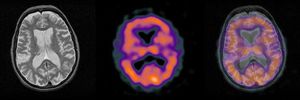

Diagnosis?

A. ALS B. Huntington’s ✅ C. Parkinson’s D. Alzheimer’s